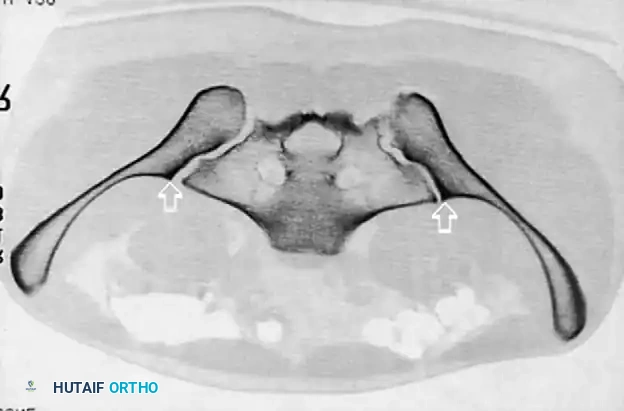

Radiographic Evaluation

Standard evaluation begins with an Anteroposterior (AP) pelvis radiograph. However, definitive surgical planning requires specialized views and advanced imaging.

• Inlet View: Directed 45 degrees caudad. Best evaluates anterior-posterior translation, internal/external rotation, and sacral impaction.

• Outlet View: Directed 45 degrees cephalad. Best evaluates vertical translation and sacral foraminal anatomy.

• CT Scan: The gold standard for evaluating posterior ring injuries, sacral dysmorphism, and preoperative planning for percutaneous fixation.